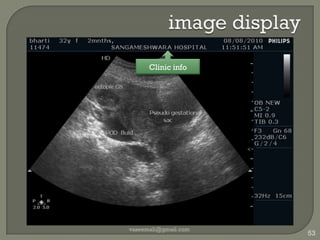

image displayvaseemali@gmail.com50

image displayvaseemali@gmail.com51Manufacturer

image displayvaseemali@gmail.com52Date/time

image displayvaseemali@gmail.com53Clinic info

image displayvaseemali@gmail.com54Patient  info

image displayvaseemali@gmail.com55Profile / Preset

image displayvaseemali@gmail.com56Transducer in use